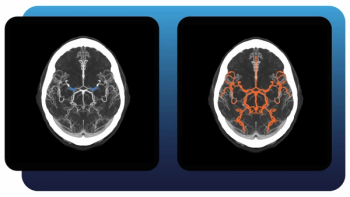

Combining multimodal imaging data and biopsy data, an artificial intelligence (AI) model provided enhanced sensitivity for defining prostate cancer tumor margins in comparison to conventional magnetic resonance imaging (MRI) assessments.